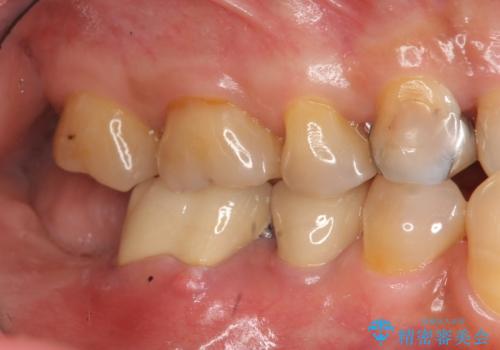

- 「奥歯で噛むと痛い、いつも膿のにおいがして不快、改善してほしい。」と治療を希望され来院されました。

精査した結果、奥歯の根は破折しており抜歯を避けられない状況でした。

咬合力が強く、その他の歯の破折も防ぐために奥歯の咬合機能をインプラントを用いて回復する治療計画を立てます。